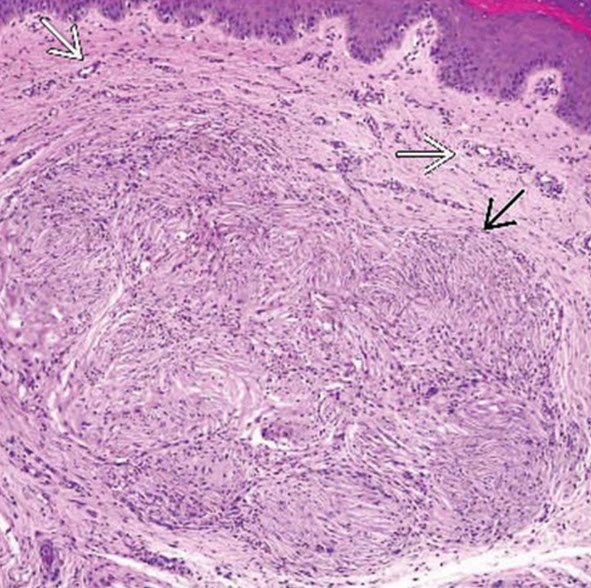

Morphea / scleroderma

Morphea (aka localized scleroderma( is the MC of the sclerosing disorders

Group of dz's, with deep dermal sclerosis always there, and can go all the way down to the bone

Rectangular punch bx c trapped eccrine glands 2/2 loss of adventitial fat, thick closely packed red ollagen bundles in lower dermis

- no interface dermatitis, but can see some inflam at lower dermal levels

- usually early signs are a superficial and deep perivascular lymphoplasmacytic infiltrate c varying amts of perieccrine inflam

- later can see collagen fibers thicken and become hyalinized and eosinophilic

- eccrine glands lose their surrounding fat and can disappear completely

Morphea

Morphea (localized scleroderma)